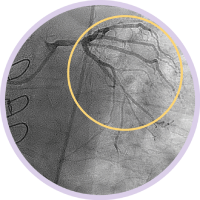

Ангиография дает сведения о характеристиках просвета сосуда, но не позволяет получить четкого изображения сосуда и поражения.

Между тем, использование ВСУЗИ помогает получить более четкую картину и улучшить результаты лечения пациента за счет планирования стентирования на основе данных и оптимизации стента после его установки1.

ВСУЗИ был присвоен класс IIa в клинических рекомендациях AHA/ACC/SCAI при оценке поражений ствола левой коронарной артерии9. ВСУЗИ помогает определить: • Значимость поражения • Размер сосуда • Оптимальное позиционирование стента